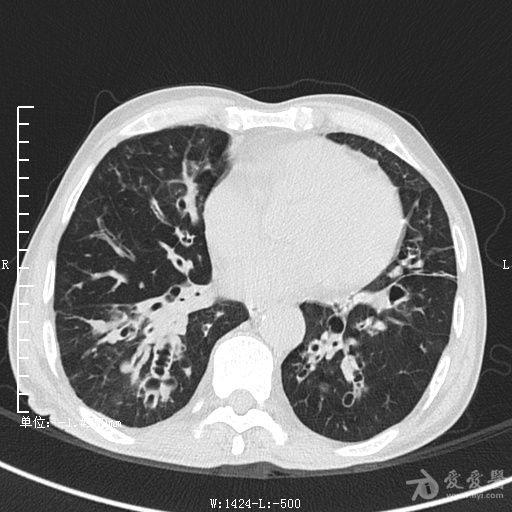

典型支气管扩张及肺水肿CT片

典型支气管扩张肺水肿